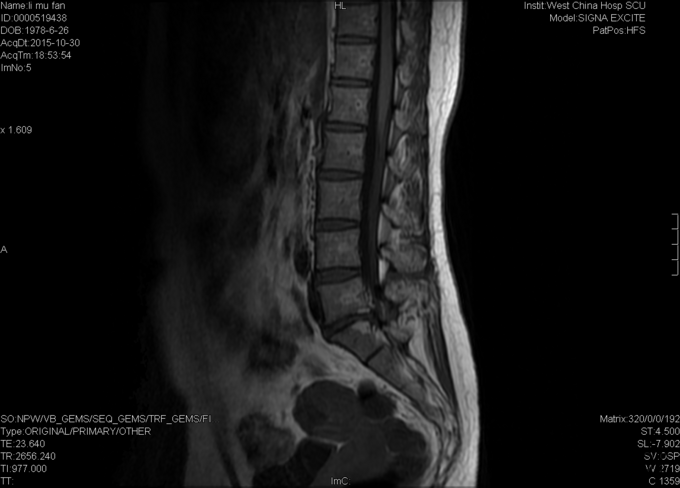

女,37岁4月,因“反复腰痛伴左下肢疼痛20+年,加重1+月”入院。20+年前患者因跌倒都出现腰部疼痛,症状反复发作,偶伴左小腿疼痛,予以牵引、针灸、按摩等治疗后症状缓解,久坐后复发。1+月前再次出现腰部及臀部疼痛,于当地医院予以对症支持后症状未完全缓解,现为求进一步治疗,遂入我院就诊。

专科检查:视:步入病房,步态无明显异常。腰椎生理弧度浅直,无明显侧弯,四肢及关节屈伸活动正常。触:脊柱腰段无明显叩痛,L4-L5、L5-S1椎旁叩痛,左臀广泛压痛,右踝外侧感觉减退,双下肢及鞍区无明显皮肤感觉减退及过敏。动量:双下肢肌力、肌张力正常,病理征(-),双侧跟腱反射正常,其他生理放射正常,余未见明确异常动量。 辅助检查:外院MRI:腰5/骶1椎间盘突出,腰5、骶1椎体异常低信号。。

初步诊断:腰5/骶1腰椎间盘突出症伴不全神经损害